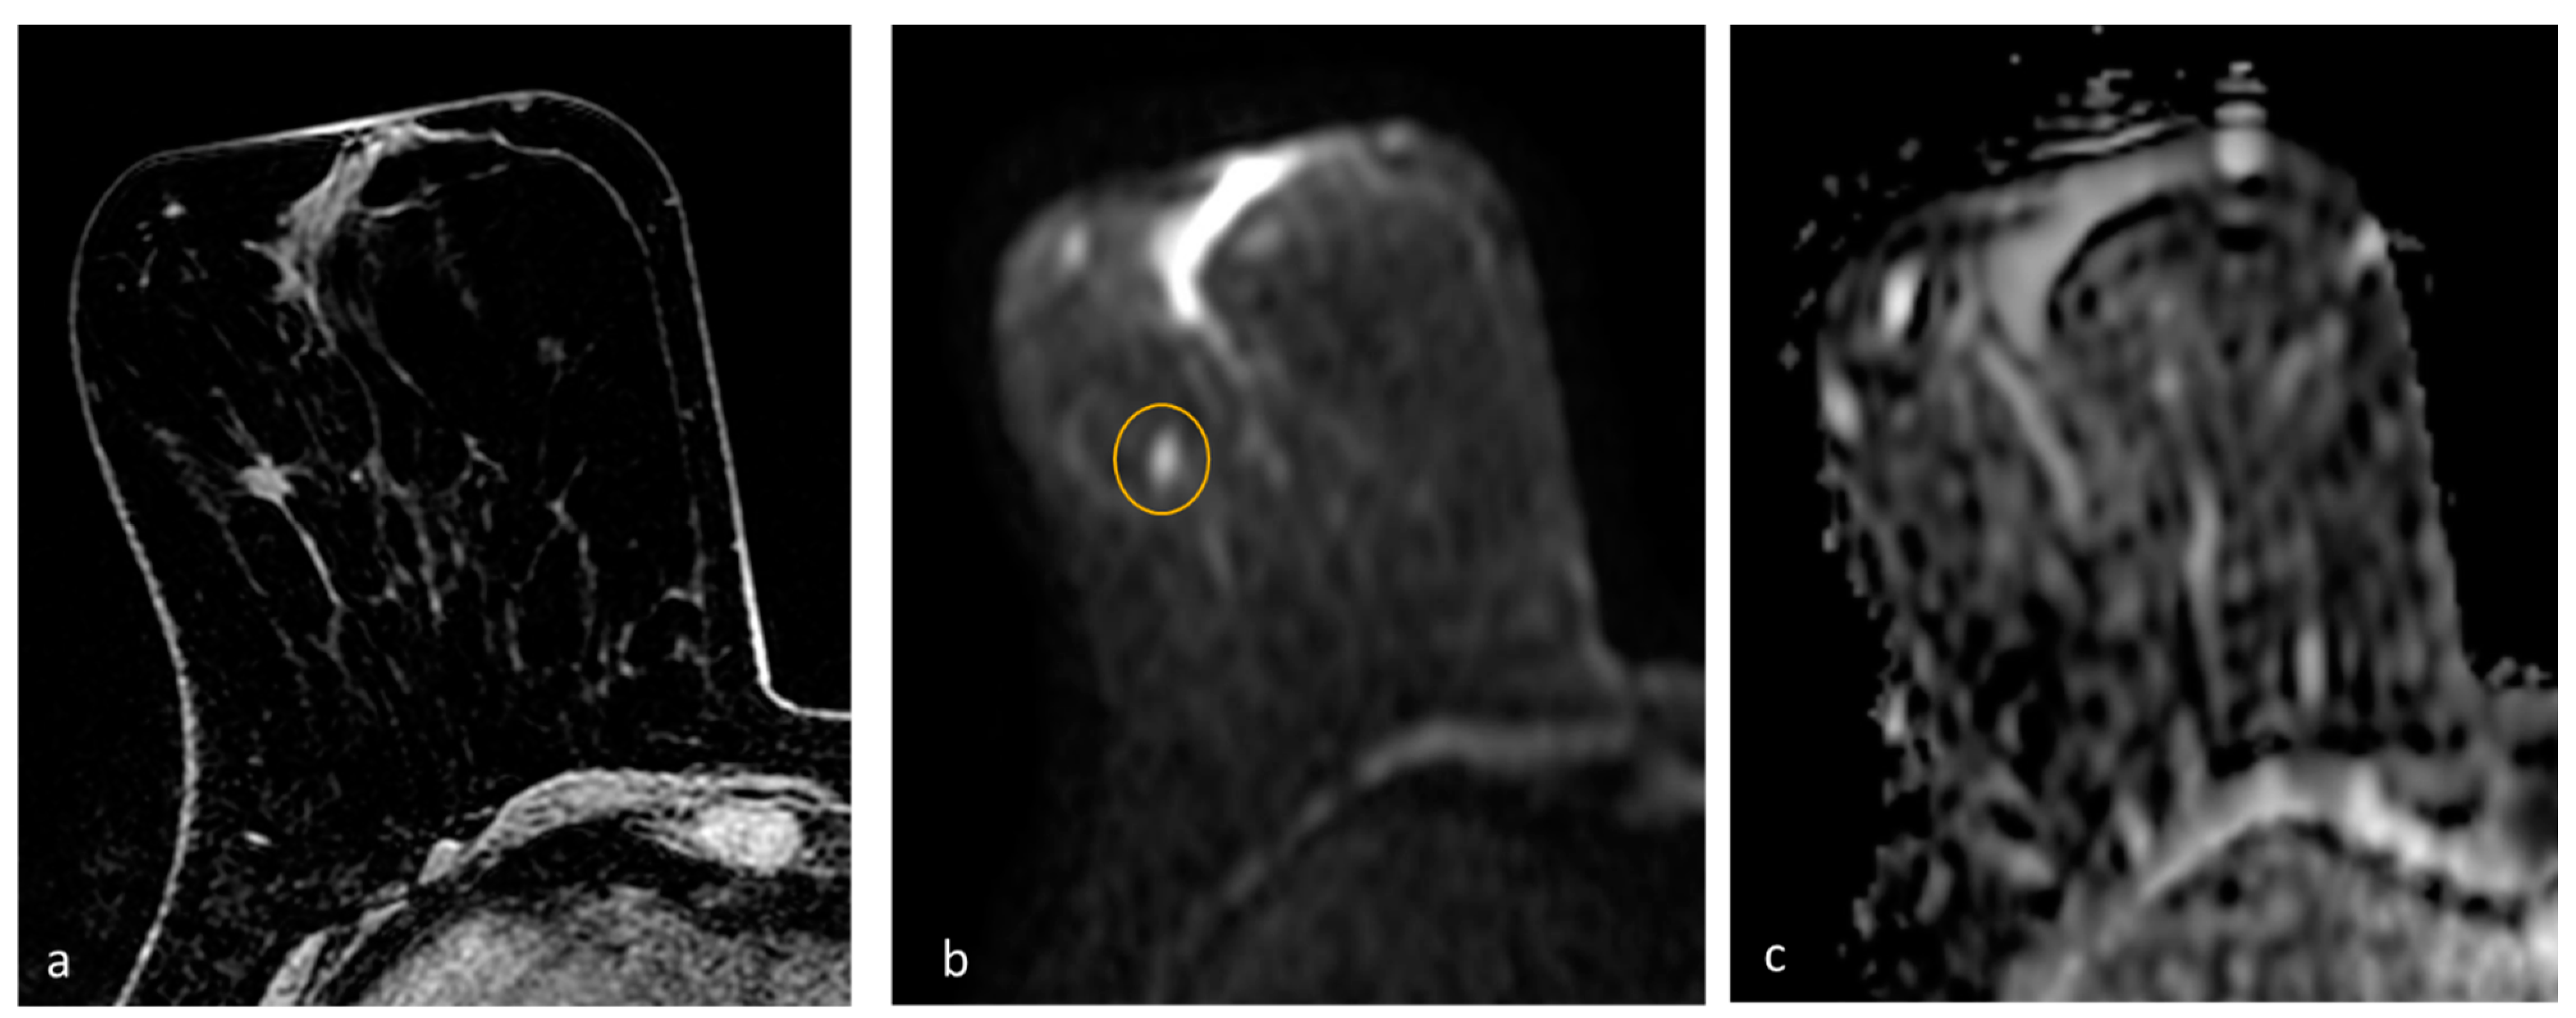

- Pesapane, F.; Rotili, A.; Penco, S.; Montesano, M.; Agazzi, G.M.; Dominelli, V.; Trentin, C.; Pizzamiglio, M.; Cassano, E. Inter-Reader Agreement of Diffusion-Weighted Magnetic Resonance Imaging for Breast Cancer Detection: A Multi-Reader Retrospective Study. Cancers 2021, 13, 1978. [Google Scholar] [CrossRef] [PubMed]